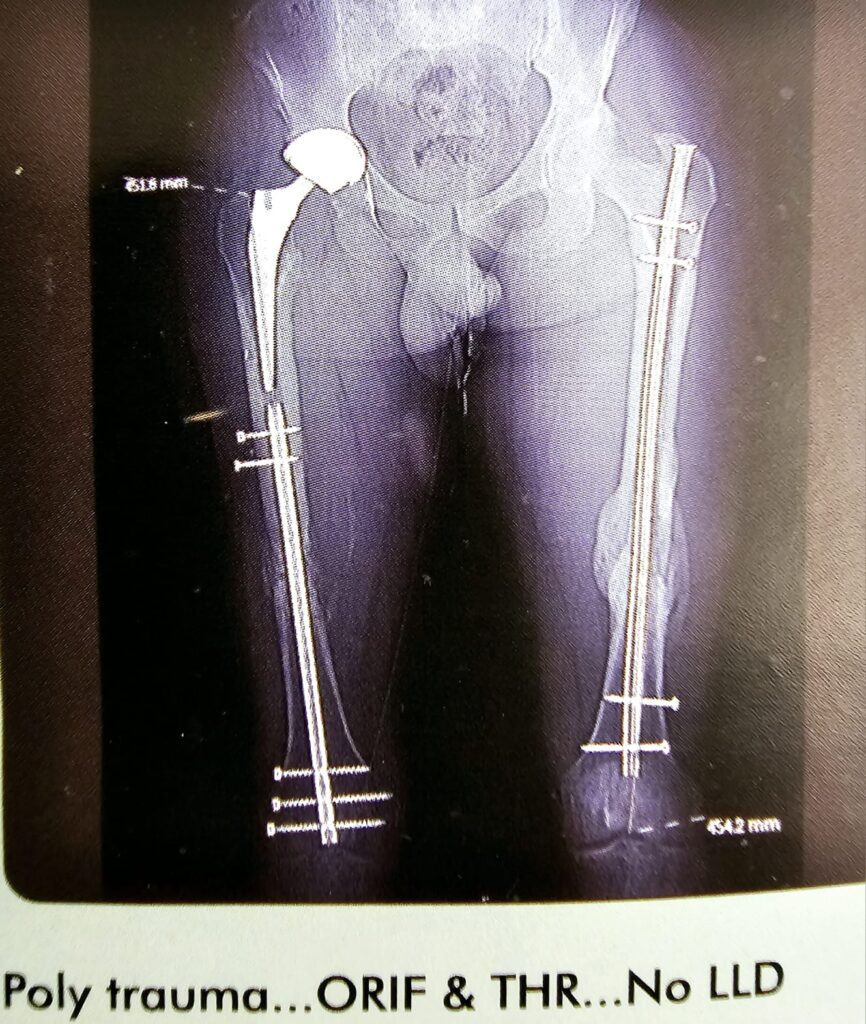

Poly trauma –ORIF &THR NO LLD

This is an interesting case of gentleman, Fracture of the right neck of femur, which was internally fixed and failed. I did took off the head and neck of the femur on the right side put in THR on the right side with the 36 mm head. And dis reverse intra medullary nail of the femur from the knee joint. Locked it both proximally and distally and on the left side of revision femur nailing was done. Patient did extremely well with no limb and discrepancies